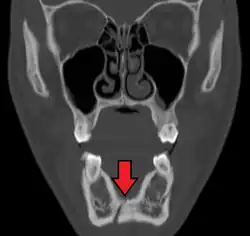

multiple mandible fractures of a patient in the right condyle (extracapsular/neck/not dislocated), right body (vertically unfavourable) and left coronoid process